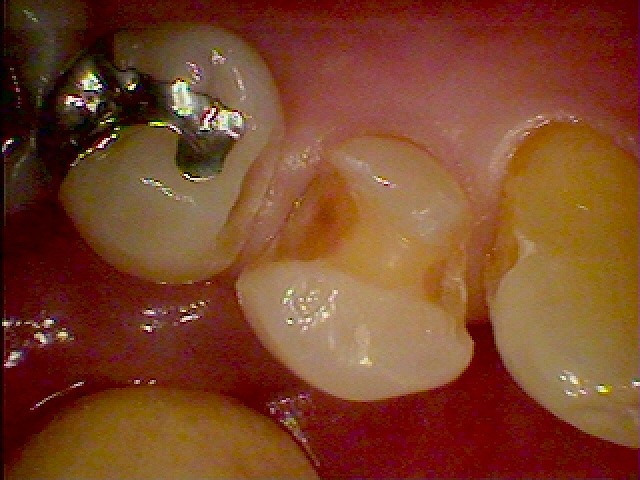

問題の銀歯になります

銀歯を外すと歯との境から虫歯になってきていました

悪いところを除去していきました

セラミックにて修復時になります

このように本来の歯のようにきれいに仕上がりました